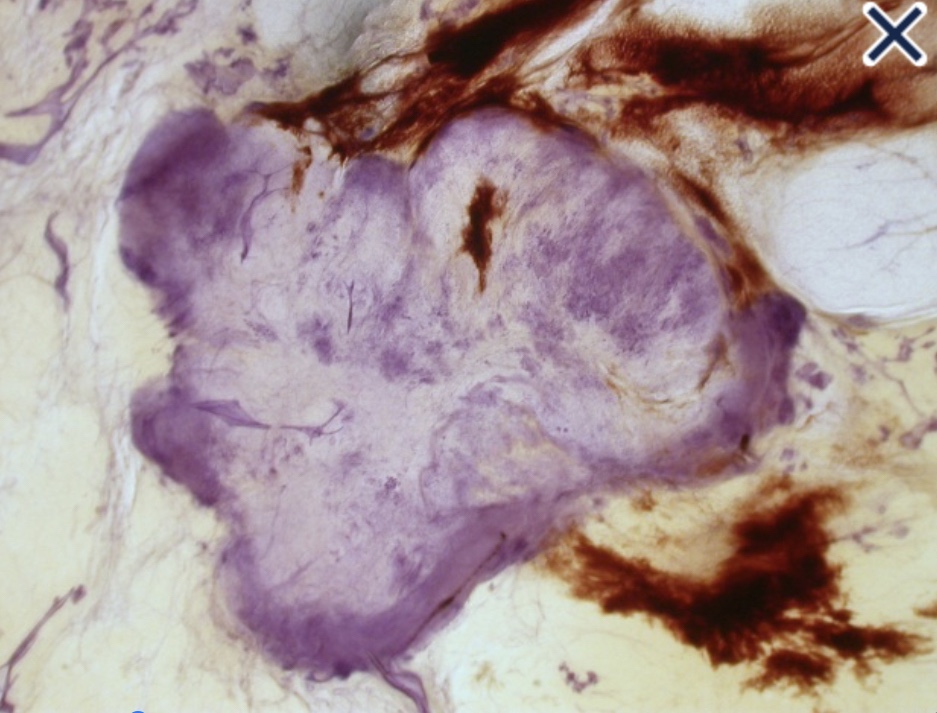

Lobulated spherical tumor mass

• Circular (Image) and spiculated (Image) tumors arising in the terminal ductal lobular units (TDLU):

• Have bulging, convex contours protruding into the adipose tissue